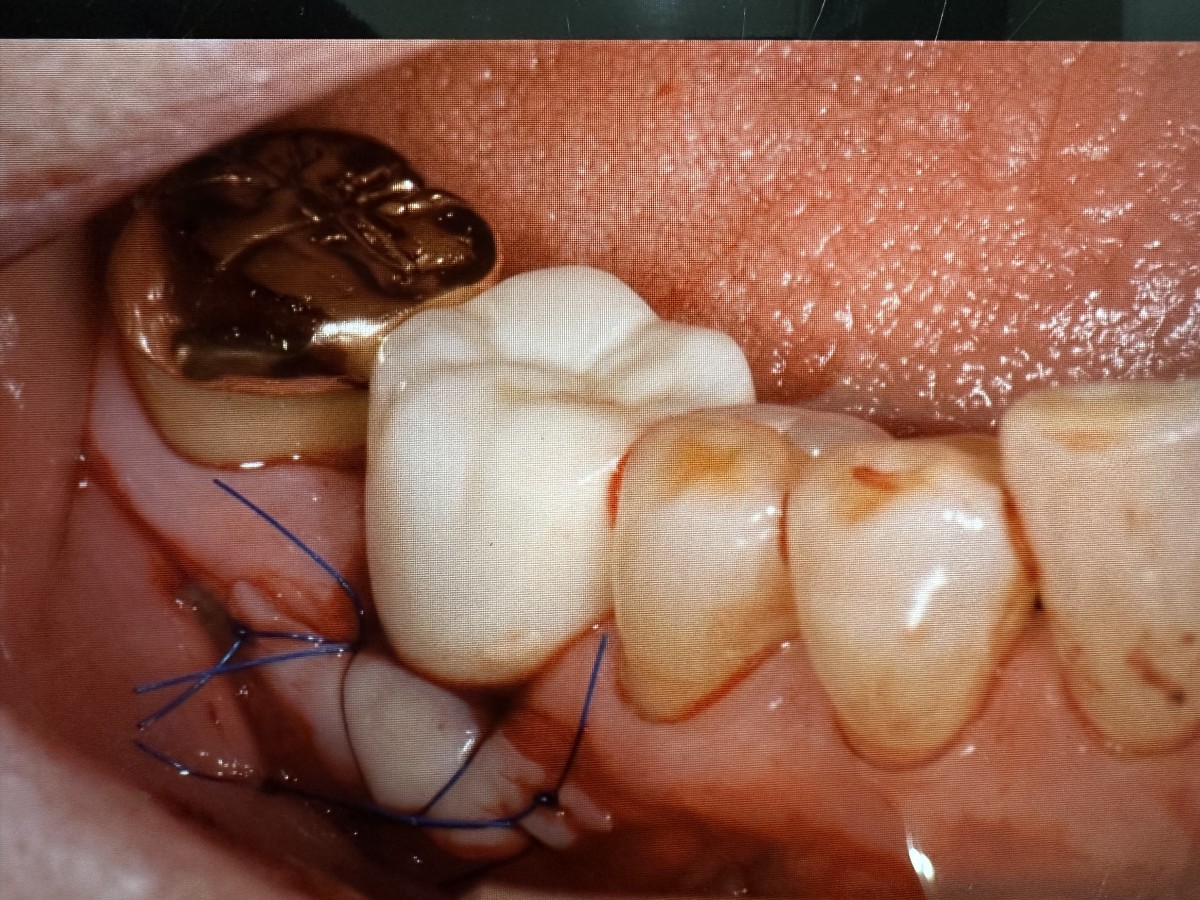

어금니잇몸이식에 관해 궁금하신것 같습니다.

-> 어금니는 앞니보다 접근이 어렵고, 전정(vestibule, 빰의 깊이)이 얕은 경우가 많아 시술이 어려운 경우가 많습니다.

어금니 잇몸이식이 모든 경우가 가능한경우는 아니라서 직접 검사후 가능여부를 말씀드릴수있을것 같습니다.

잇몸이식비용은 보험절차가 있어 첫날 간단한 치석제거 후 다음내원때 이식하게 되며 비용은 보험비용을 5-8만원되며, 입천장 공여부 잇몸지혈장치비용 10만원 비용이 듭니다.

수술후 2주뒤 실밥을 풀게 되며 일상생활에 지장은 없습니다. 감사합니다.